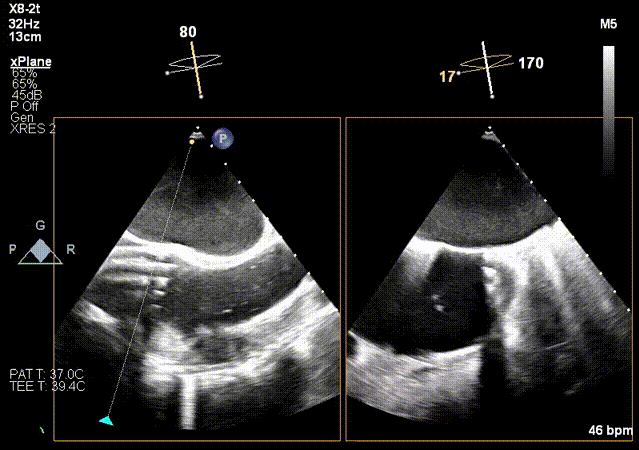

3.超声MPR模式下攻入锚定部件。

MPR下攻入锚定部件